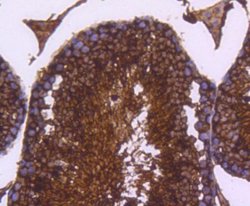

Lactate Dehydrogenase A/LDHA Monoclonal specifically detects Lactate Dehydrogenase A/LDHA in Human, Mouse, Rat, Zebrafish samples. It is validated for Western Blot, Flow Cytometry, Immunohistochemistry, Immunocytochemistry/Immunofluorescence, Immunoprecipitation, Immunohistochemistry-Paraffin.Specifications

| Western Blot 1:1000-1:5000, Flow Cytometry 1:50-1:100, Immunohistochemistry, Immunocytochemistry/Immunofluorescence 1:50-1:200, Immunoprecipitation, Immunohistochemistry-Paraffin 1:200-1:2000 | |